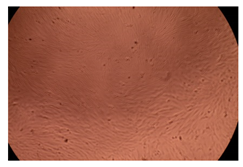

The results of the cytotoxicity assay, given in Figure 5, indicate that the tested PMs at all three established concentrations (10, 50, and 100 µg/mL) did not show cytotoxic effects on fibroblast cells at either 24 or 48 h after incubation. The percentages of cell viability were high, over 90%, in cells that were exposed to a concentration of 10 µg/mL for 24 h for all tested materials. Even at 48 h after incubation, the percentage of cell viability was as high as 90.4% in cells exposed to a concentration of 10 µg/mL for the Cop B sample. For both drug-loaded PMs, the cell viability decreased slightly at all tested concentrations. It also appears that the Dorzolamide-loaded PMs have slightly lower cell viability as compared to IMC-loaded PMs. Micrographs of the fibroblast cells after incubation times of 24 and 48 h are provided in Table 2.

Table 2.

Micrographs of fibroblast cells after 24 and 48 h incubation times, respectively.

As the cell viability values are all over 80%, the results indicate that the PMs, at the established concentrations, can be used successfully for in vivo biomedical applications.